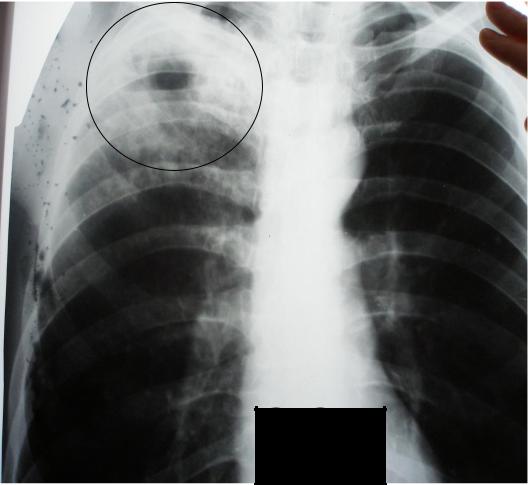

Иллюстрации по теме очагового и инфильтративного туберкулеза

Раздел: Фотодневник открытий